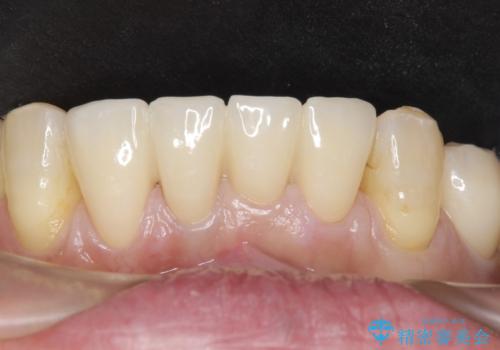

[ジルコニアクラウン] 前歯の見た目を良くしたい

![[ジルコニアクラウン] 前歯の見た目を良くしたいの症例 治療後](https://seimitsushinbi.jp/wp/wp-content/uploads/2021/06/65789acde6152d35c473703d5d39acaf-500x350.jpg?v=1623380236)